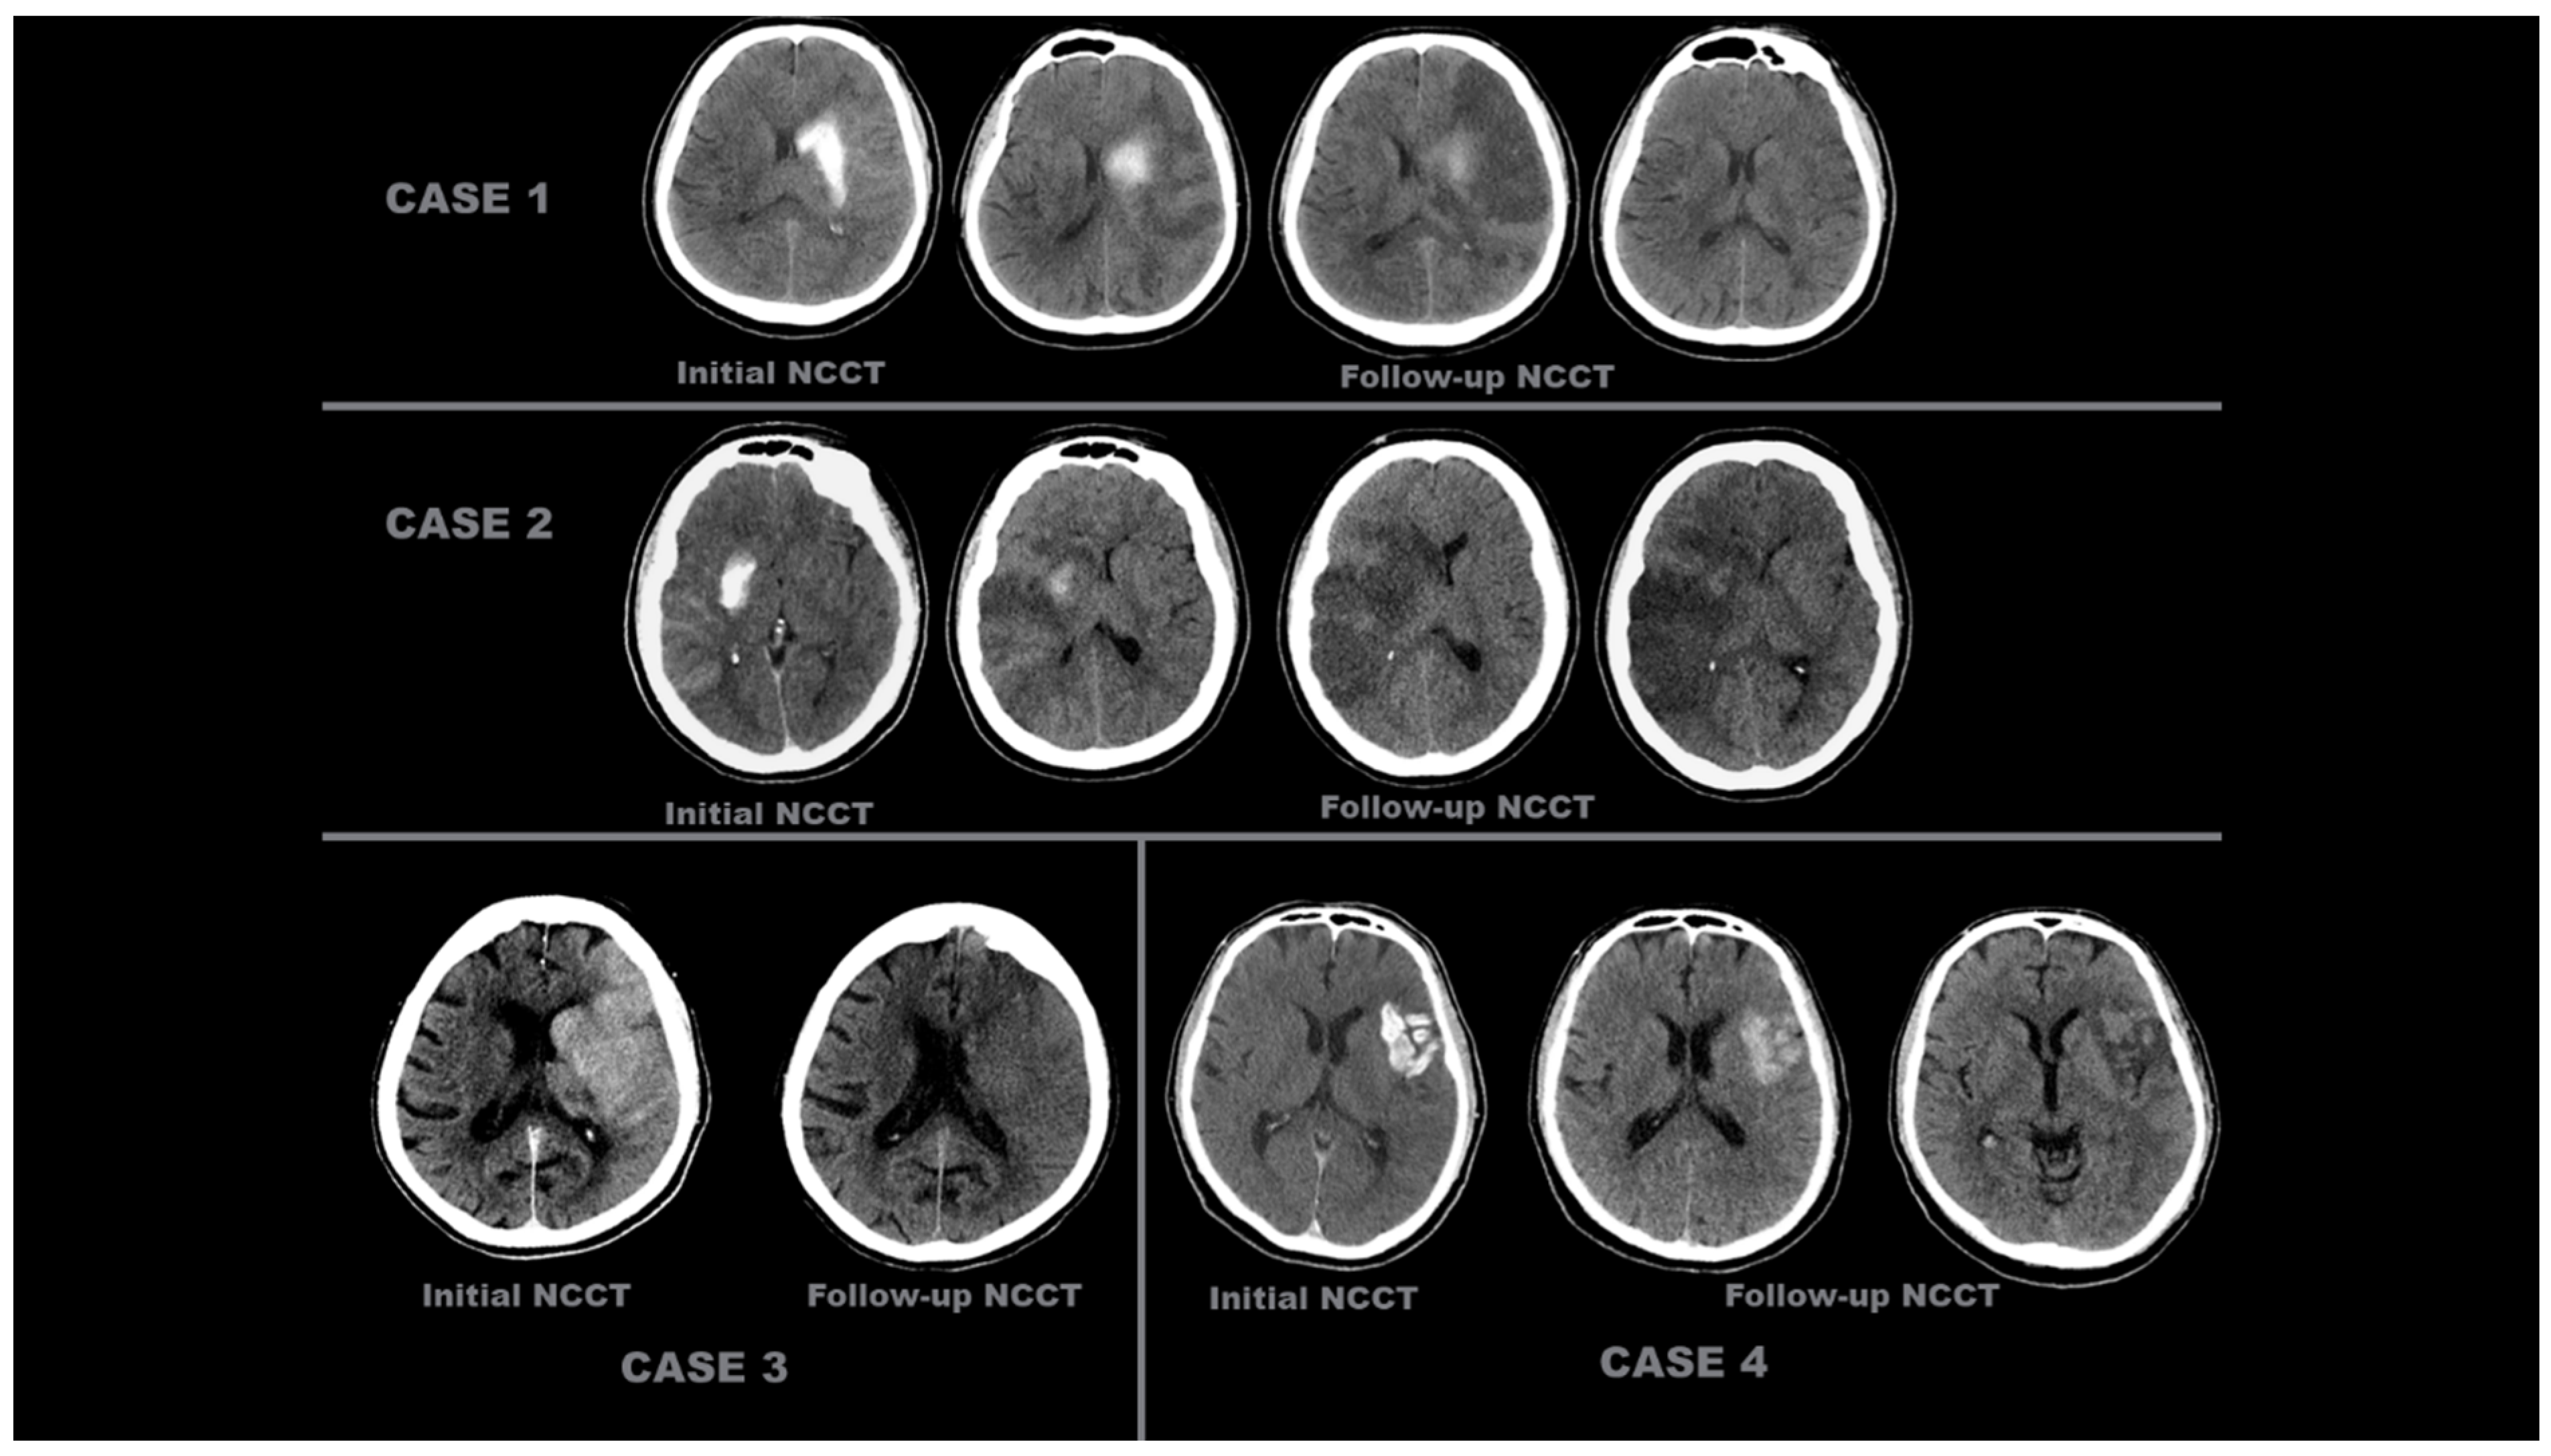

- Contrast Accumulation: The first scan found in the NCCT and the follow-up scan in the NCCT met all of the following conditions;

- Sequential follow-up scan showed hyperdensity that completely disappeared without leaving a hematoma area.

- Sequential follow-up scans show no newly developed hyperdense area.

- In sequential follow-up scans, hyperdensity that gradually decreases and completely disappears in NCCT images after 72 h.

- Hemorrhagic Transformation: The initial scan shows NCCT, and the follow-up scan shows NCCT meeting any of the following conditions.

- Hyperdensity that does not decrease or remains constant.

- Increase in hyperdensity size.